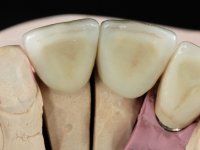

Patient male, 60 years old, non-smoker. After imaging and clinical examination, it was found that the patient had teeth 2.1 and 2.2 with extensive acrylic restorations, with screwed intra radicular posts and very poor endodontic treatments. Tooth 2.2 had an extensive apical lesion, the post had been placed on a false route and had mobility. Tooth 1.1 had an extensive resine restoration and tooth 1.2 presented a mesial restoration, also in composite resin, Class III type. The antero-superior sector was vestibularized, as consequence of a loss of vertical occlusion dimension associated with posterior edentulism. The patient showed reasonable periodontal health and satisfactory oral hygiene.